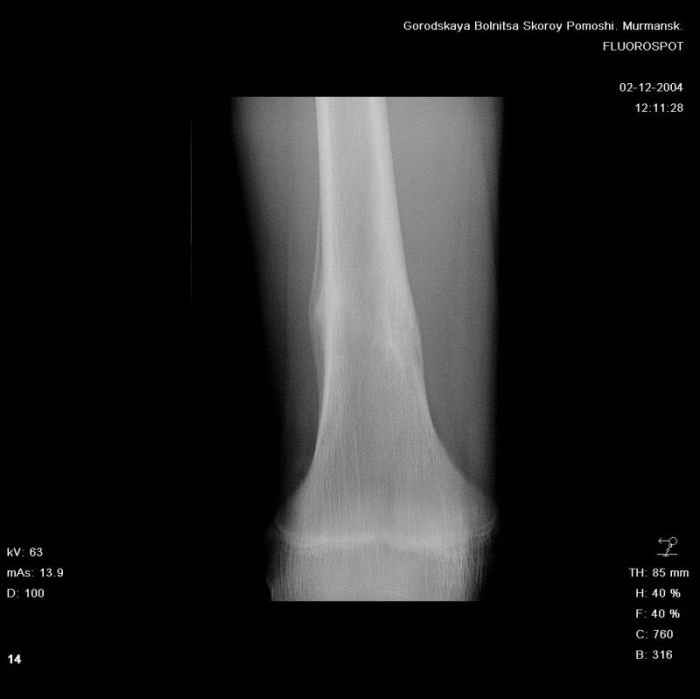

Здравствуйте, уважаемые коллеги!Представляю вашему вниманию интересный случай и пока что непонятный для меня в диагностическом плане. На днях в наше отделение (детской ортопедии и травматологии) поступил 13-летний мальчик по направлению из поликлиники с диагнозом: остеома нижней трети правого бедра.

Анамнез практически никакой: в следствие травмы (растяжение связок коленного сустава) от 07.11.2004 выполнены Rg-граммы в травмпункте и обнаружено опухолевидное образование. Первичные Rg-граммы я не публикую, так как они заметно худшего качества, да и динамики за прошедшие три недели не отражают. Болевой синдром купирован в течение трёх дней. В настоящий момент мальчика ничего не беспокоит. Ходьба не нарушена, опухоль пальпируется с трудом по задней поверхности в н\3 правого бедра, пальпация безболезненна, объем движений в суставах правой нижней конечности полный и симметричный. Кожа над опухолью не изменена.В нашей клинике проведено дополнительное обследование: общие анализы крови и мочи, биохимия крови без особенностей. Выполнены Rg-граммы на цифровом Siemens обычные и продольные томограммы срезами 3-5 мм, а также компьютерная томография поперечными срезами по 5 мм. Прошу обратить внимание, что на приведённых томограммах видны две полости 10х15 мм и 15х60 мм. Также имеются два опухолевидных образований наслаивающихся друг на друга: уплощённое и вытянутое 10х100 мм и элипсовидной формы 15х30 мм. Это хорошо заметно на фото a_1.jpg c_1.jpg и d_1.jpg. Плотность внутри полостей 125% от плотности костномозгового канала, плотность наружного опухолевидного образования 55% от плотности кортикального слоя. Также отмечается линия перелома по центру наружного опухолевидного образования.Исходя из полученных данных мнения в плане диагноза несколько разделились от 1)сочетания кортикальной фиброзной дисплазии и латентно протекавшего маршевого перелома н\3 правого бедра до 2)остеосаркомы. В отношении первого варианта не сходится отсутствие клиники при переломе такой крупной кости как бедро, второй вариант вообще оставлю без комментария, ибо некомпетентен. Хотелось бы услышать мнения коллег, с удовольствием ознакомлюсь с любыми предположениями и замечаниями.С уважением, Александр Е. КлоковОтделение детской ортопедии и травматологииБСМП г. Мурманска.

С облегчением спешу сообщить, что гистологический анализ подтвердил сложившееся интраоперационно мнение, что мы имеем дело с посттравматической перестройкой костной ткани (костной мозолью). Плюс к этому фиброзные кортикальные дефекты. В обшем, зла нет и слава Богу.